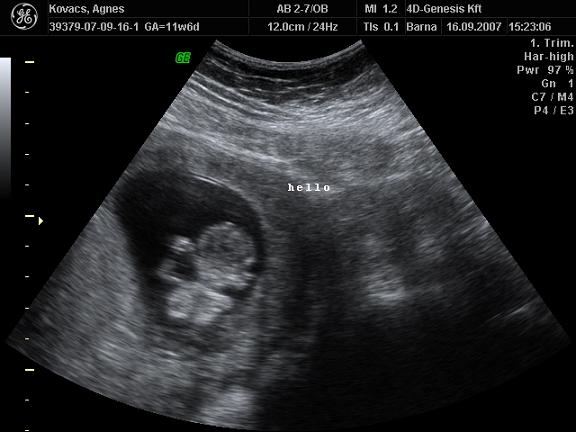

Nos nem tudom, hogy ti mennyire latjatok:

Eleg rosszul latszik, de itt ket vonal van:

Itt meg egy kiallo valami:

Amit lattam az szerintem fiu lesz, hiaba erzem, hogy lany.

A masodik kepen itt nem latszik jol csak a rendes tv-n egyertelmuen olyan mint Zolie volt.

Hiaba van sok helyen ket csikocska.

Nem volt 4D sem es 3D sem, mert meg pici es nagyon eletlen volt.

De igy megusztuk a fele arert.

1 ora volt az UH es vegig mozgott, de beterpeszteni nem akart, ezeket veletlenul csipte el.

A szivet is nehezen lehetett meghallgatni, mert egyfolytaban elugralt.